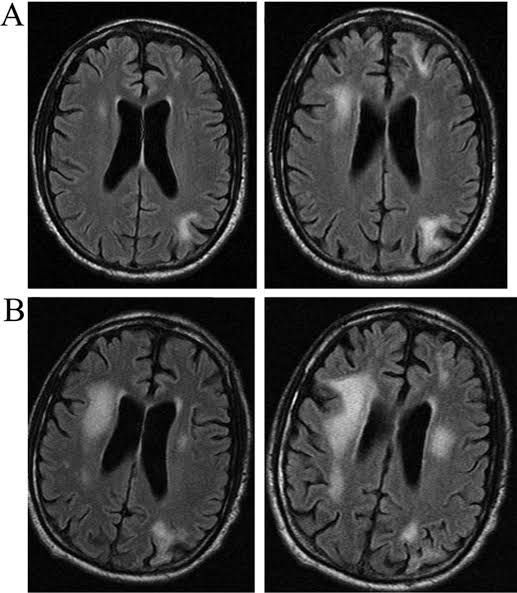

Progressive multifocal leukoencephalopathy (PML) is a disease of the white matter of the brain, caused by a virus infection (polyomavirus JC) that targets cells that make myelin—the material that insulates nerve cells (neurons). Polyomavirus JC (often called JC virus) is carried by a majority of people and is harmless except among those with lowered immune defenses. PML is rare and occurs in people undergoing chronic corticosteroid or immunosuppressive therapy for organ transplant, or individuals with cancer (such as Hodgkin's disease or lymphoma). Individuals with autoimmune conditions such as multiple sclerosis, rheumatoid arthritis, and systemic lupus erythematosus—some of whom are treated with biological therapies that allow JC virus reactivation—are at risk for PML as well. PML is most common among individuals with HIV-1 infection. The most prominent symptoms are: Clumsiness Progressive weakness Visual, speech, and sometimes personality changes A diagnosis of PML can be made following brain biopsy or by combining observations of a progressive course of the disease, consistent white matter lesions visible on a magnetic resonance imaging (MRI) scan, and the detection of the JC virus in spinal fluid.